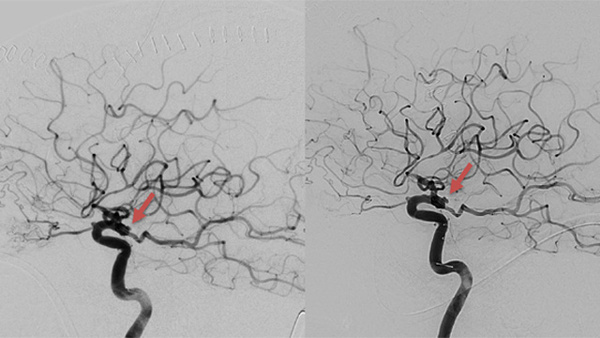

Complex, Rapid Recurrence of Clipped Ruptured Posterior Communicating Artery Aneurysm: Endovascular Management Strategy